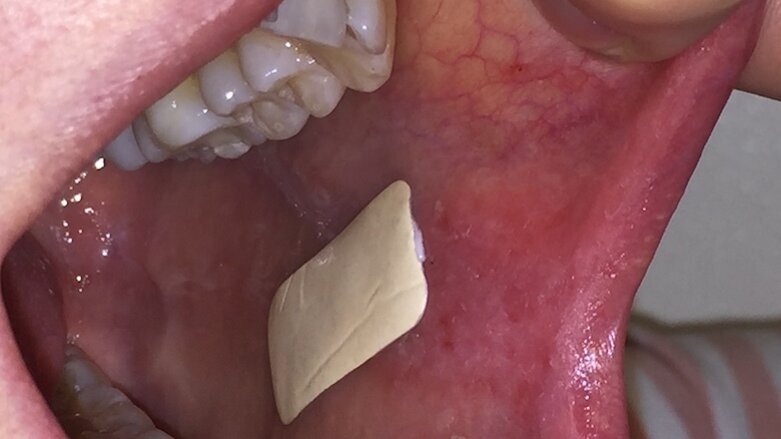

O adesivo é feito usando a tecnologia de eletrofiação. Aqui, a droga - neste caso, o clobetasol - é incorporada em fibras poliméricas muito finas que formam uma rede semelhante à malha quando o adesivo é feito. Isso cria um adesivo com uma área de superfície muito grande, que, juntamente com polímeros adesivos especialmente selecionados, permite que o adesivo adira às superfícies úmidas da cavidade oral. É um pouco como os pêlos dos pés de uma lagartixa - eles fornecem uma grande área de superfície para que eles possam grudar nas paredes e depois escalá-las. Uma vez aderida, a umidade na superfície da mucosa oral interage com os polímeros, causando a liberação do esteroide ou da droga diretamente no tecido doente. Como o adesivo possui uma camada de suporte, a liberação do esteroide é unidirecional - somente no tecido - e nenhum é liberado na cavidade oral. Isso significa que o tecido saudável não entra em contato com a droga.

O adesivo oferece liberação direcionada de drogas diretamente no tecido doente. Nossos dados mostram que o adesivo permanecerá na superfície da mucosa por muito mais tempo do que qualquer outro tratamento atual. Isso faz com que o tempo de contato entre a droga e a lesão oral seja maior do que qualquer outro método atualmente utilizado, proporcionando maior benefício terapêutico. O contato próximo do adesivo e da lesão por um período mais longo também pode significar que, em comparação com nossos métodos atuais, menores quantidades de medicamentos são necessárias para tratar lesões.